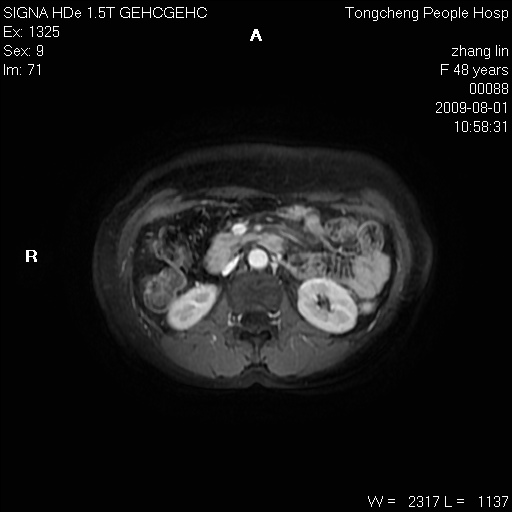

女,48岁。健康体检,彩超发现右肾占位性病变。平素健康。

临床诊断:右肾占位性病变,性质待定(囊肿?肿瘤?)。

上中腹部mr平扫+增强扫描,图像如下:

右肾上极见一类圆形病灶,t1wi呈等信号t2wi呈等高混杂信号,三期增强无强化,边界清---考虑囊肿出血。

同反相位均表现为等信号,病变无强化,考虑含蛋白的囊肿可能,弥散加权相或许有些帮助,

慢性胆囊炎